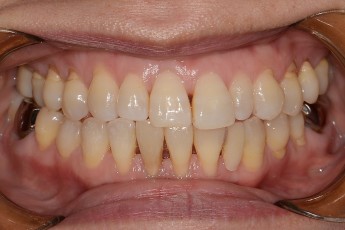

Before

After